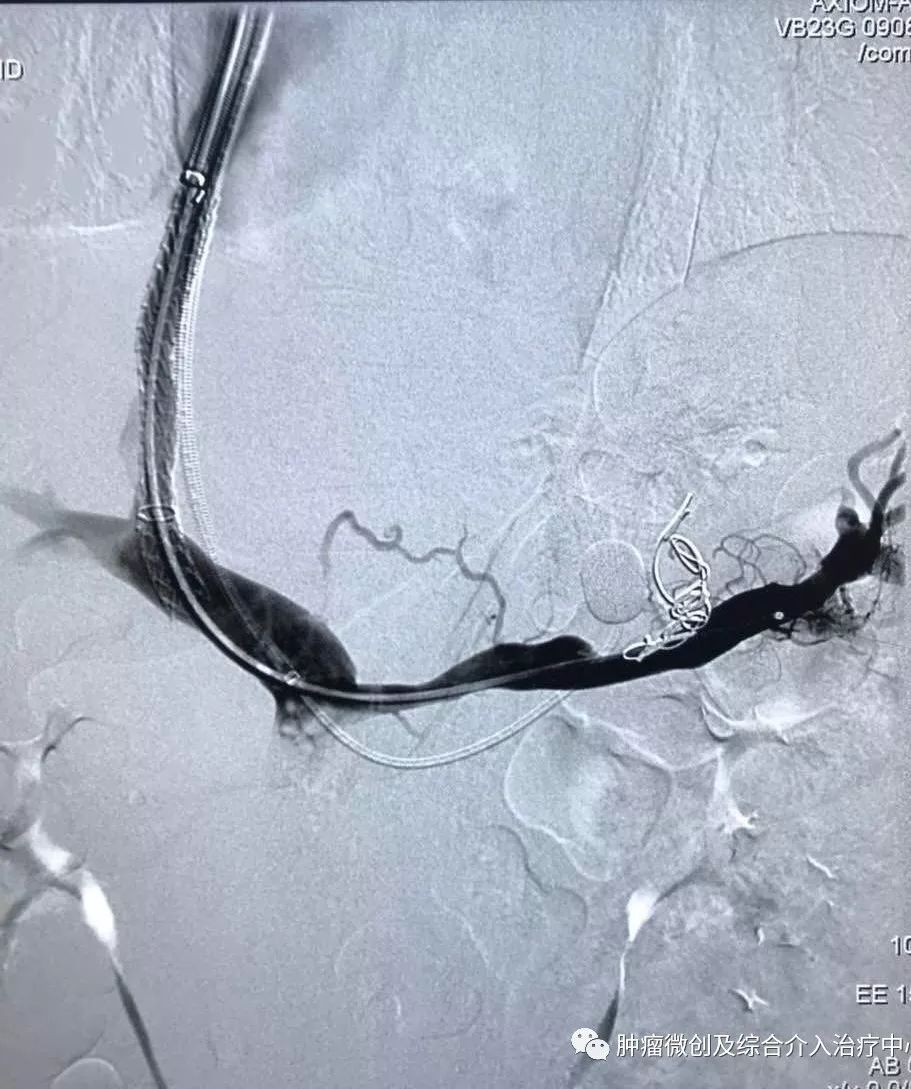

(经皮穿肝-门静脉穿刺成功,门脉高压,门静脉扩张明显)

运城第一医院肿瘤介入科专家,运城市第一医院介入科专家

(食管胃底静脉栓塞术,在血管根部将破裂的上消化道出血血管栓塞完全,即可止血)项目简介:肝硬化门脉高压失代偿期临床表现为反复消化道出血等,患者一般情况欠佳,传统治疗难以改善。食管胃底静脉+胃冠状静脉栓塞术暨经皮肤穿门脉食管胃底+胃冠状静脉栓塞明显降低因消化道大出血导致休克及死亡的风险; 结合内科治疗,其顽固性腹水症状可迅速消退,改善患者生活质量。10肝硬化门脉高压失代偿介入治疗(TIPS术)